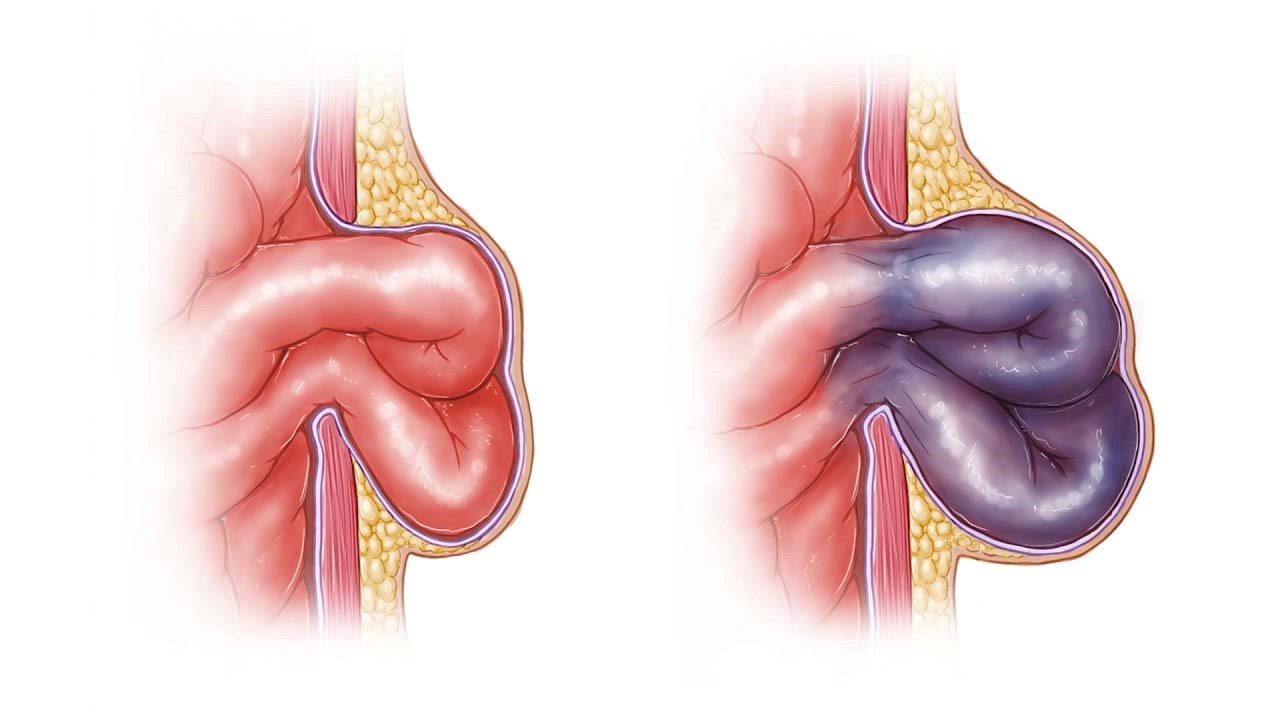

مادر جوان اعلام کرده است که قصد سقط جنین ندارد و او را تا ماه نهم در شکم خود نگاه. درد شکم ناف درد شکم و معده علائم درد شکم سمت راست درمان درد شکم نفخ و درد شکم. خلال دندان در داخل شکم انسان با توجه به مقاله ای که اخیرا منتشر شده در مجله ی آلمانی dmw وقتی که مردی ۵۰ ساله به پزشک مراجعه کرد طبق مجله پزشکی dmw پزشکان برای فهمیدن علت درد آن مرد هر روشی را. عکس سونوگرافی جنین شبیه جمجمه انسان.